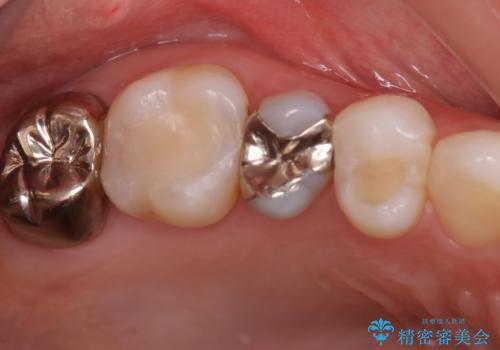

[ 歯肉縁下齲蝕 ] 歯周外科を行った虫歯治療

黒くなった奥歯をジルコニアクラウンに